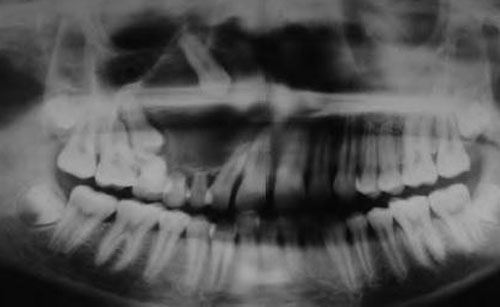

Остеогенная опухоль челюсти

- Боли в зубах, усиливающиеся ночью.

- Потеря зубов.

- Отек лица и сниженная чувствительность в области опухоли.

- Симптомы интоксикации и повышенная температура тела.

- Затрудненное дыхание на последней стадии.

Диагностика остеогенных сарком основывается на рентгенологических и гистопатологических данных. Полный набор методов обследования может включать следующие процедуры:

- Рентгенографическое исследование.

Рентгенография позволяет определить:

- местоположение опухоли;

- наличие склеротических и литических очагов, а также васкуляризацию;

- патологические изменения в мягких тканях, связанные с костями;

- образования на надкостнице в виде “козырьков” и “треугольников Кодмена”;

- игольчатые периоститы, представляющие собой разрастание игольчатых структур перпендикулярно к костям;

- макрометастатические процессы.